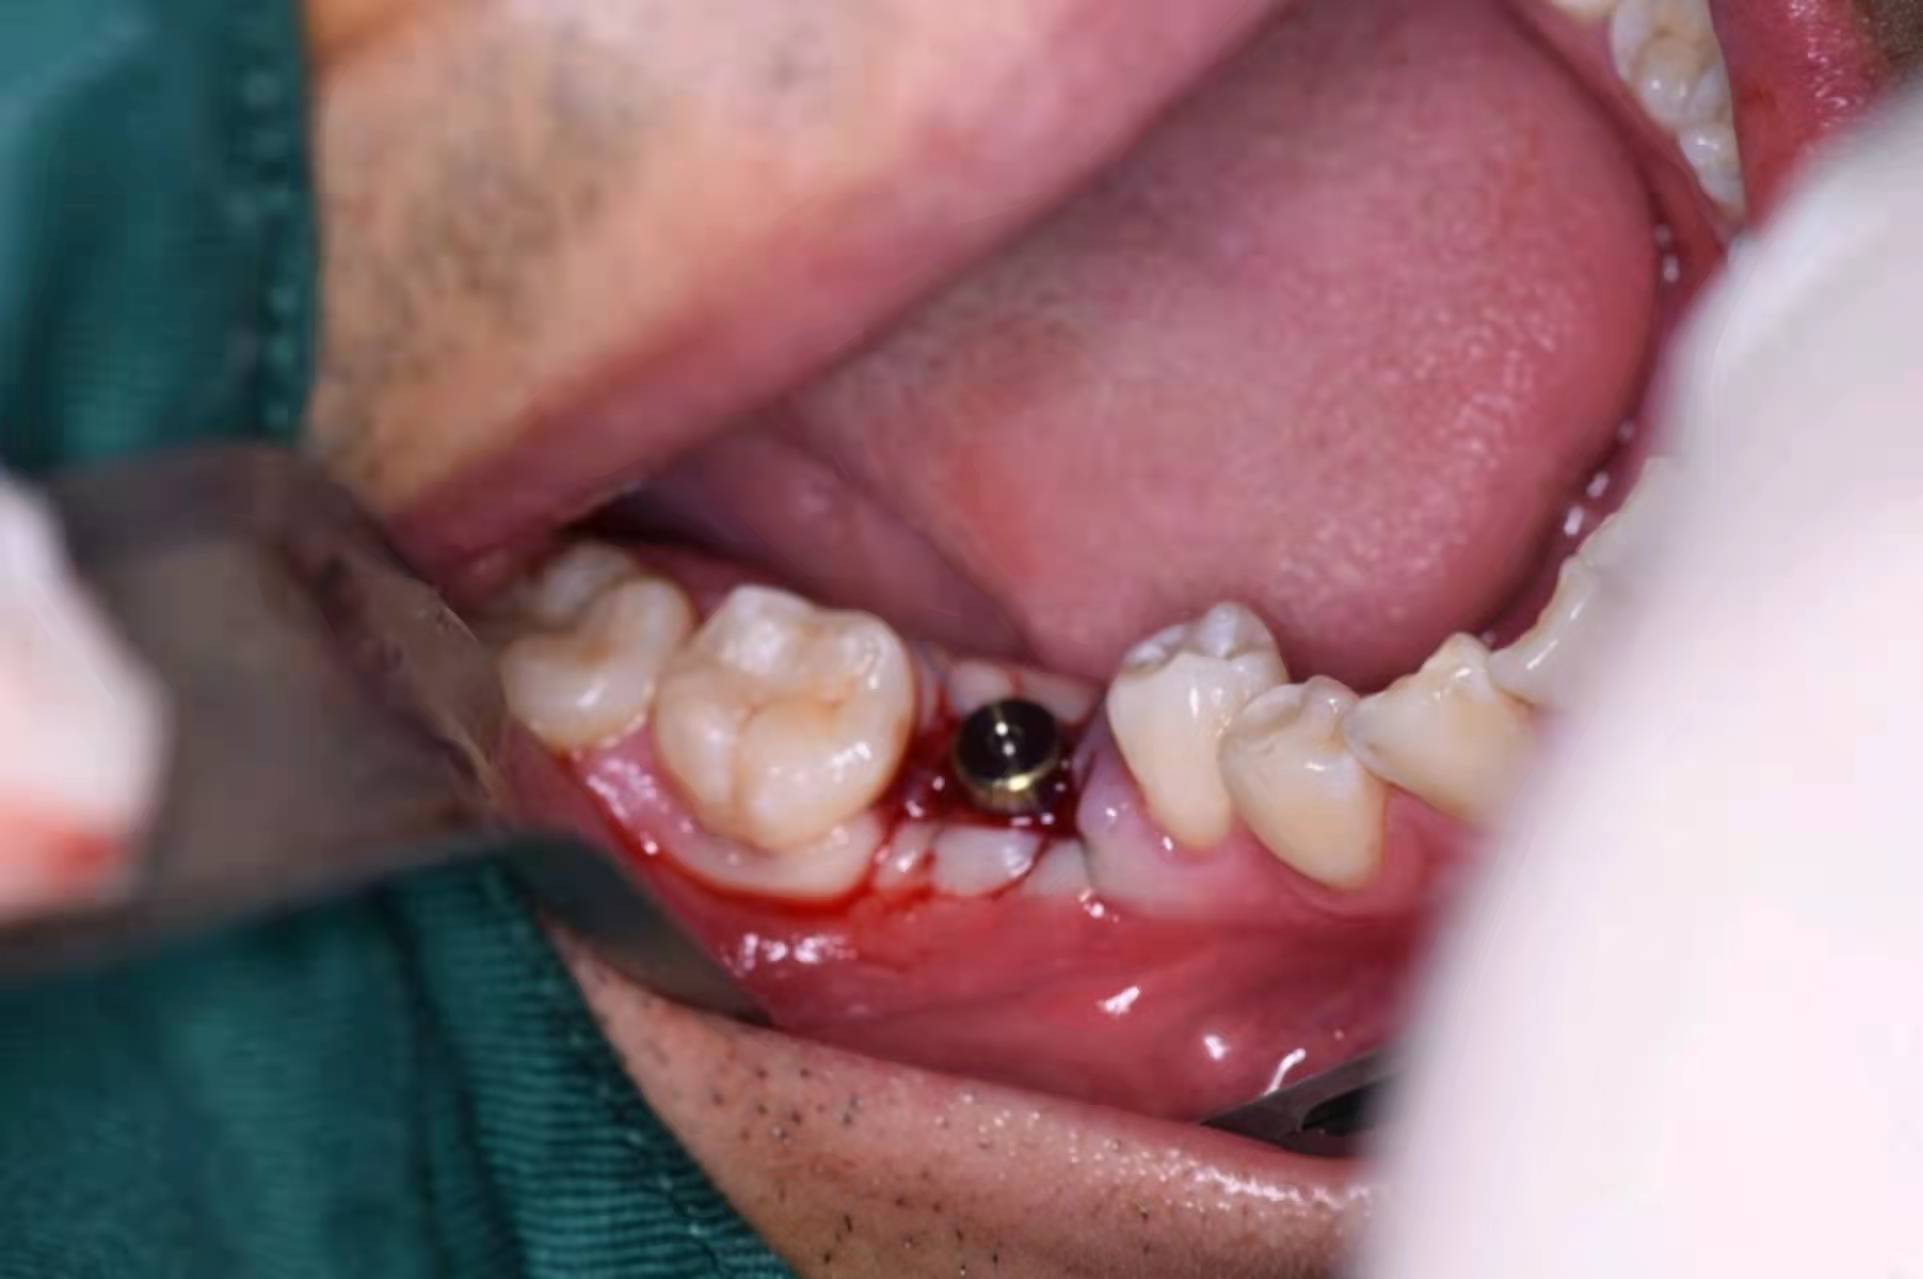

植入種植體(諾貝爾)

擰入愈合基臺(tái):